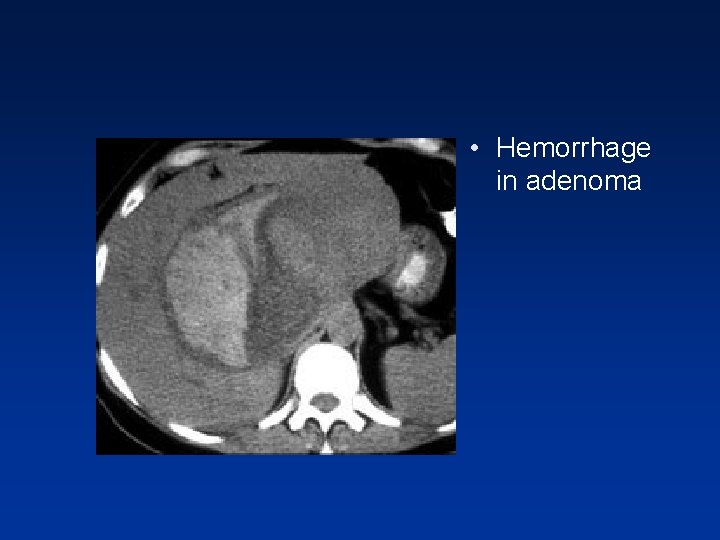

• Female with acute abdominal pain • On portal phase, hypodense hepatic lesion with hemorrhage adjacent to it, extending subcapsularly.

• Fat in adenom a

• Hemorrhage in adenoma